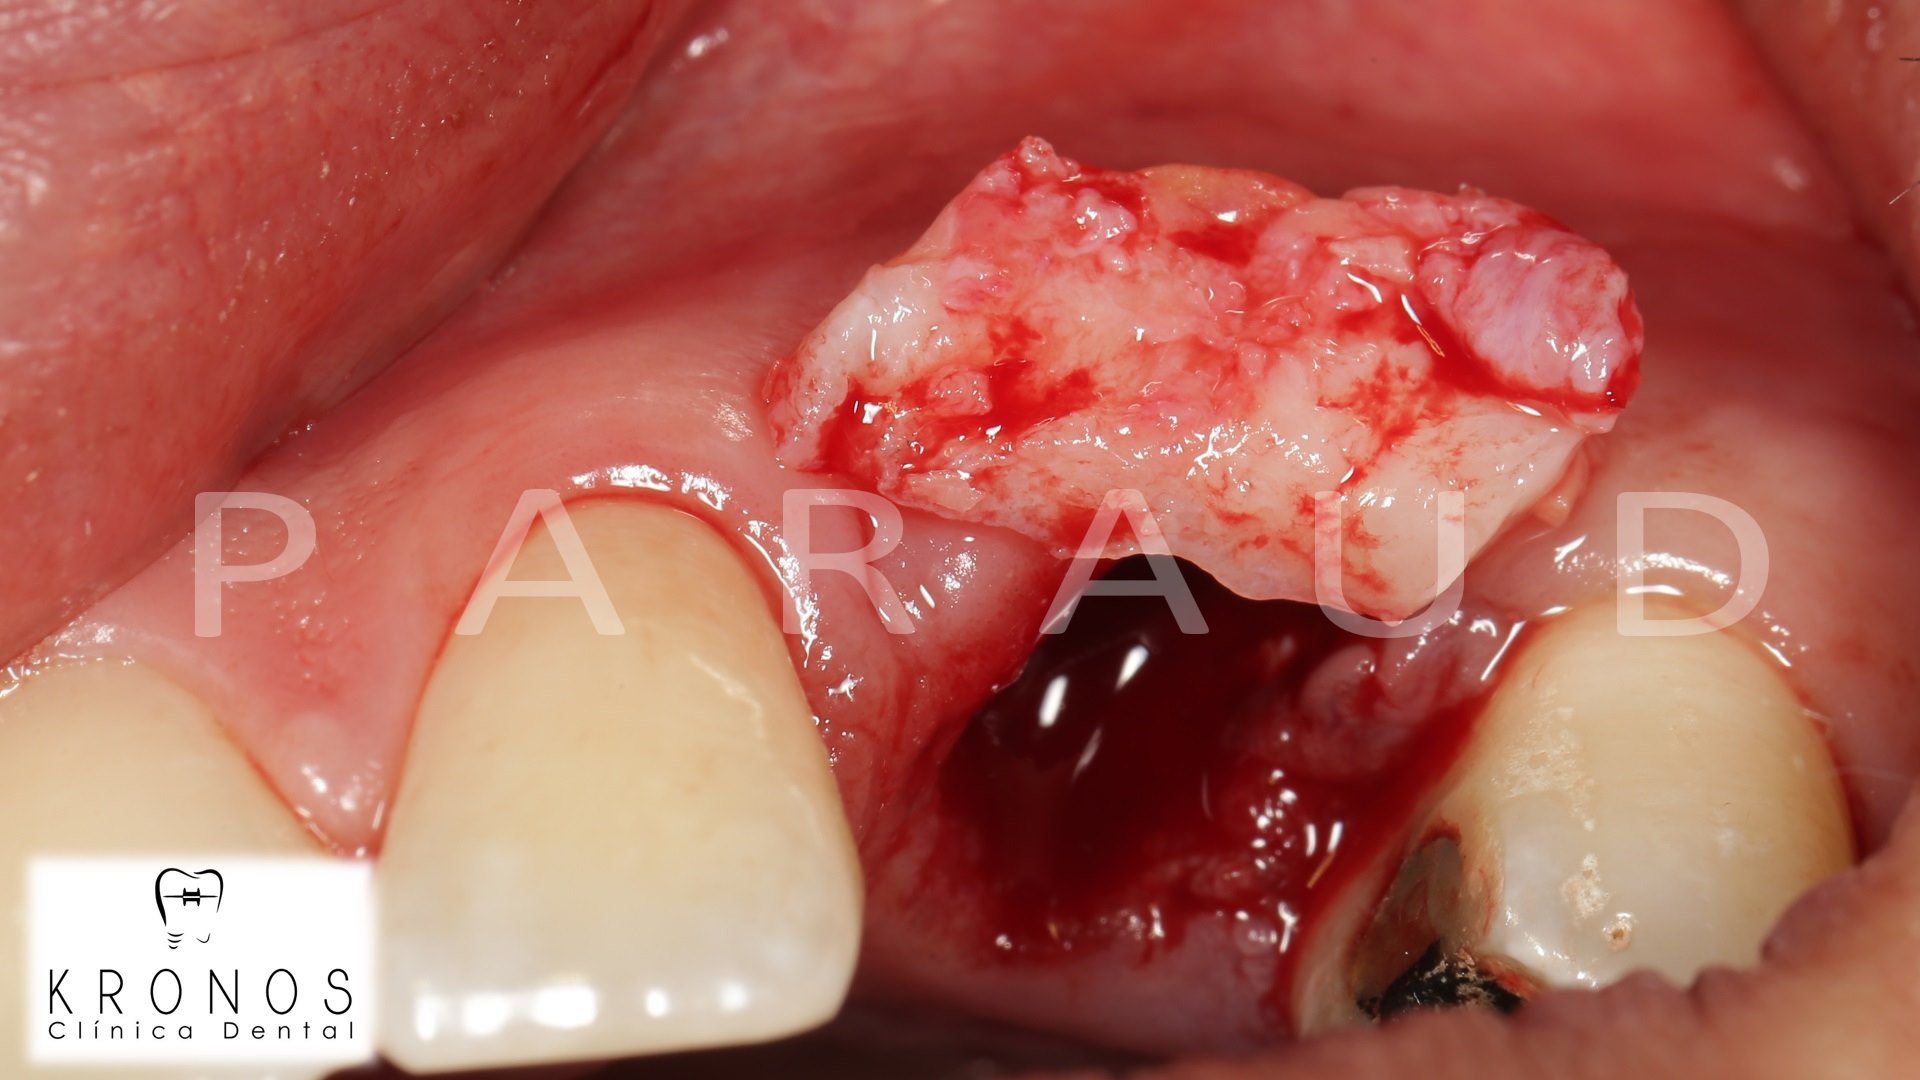

Clinical case: AnyRidge immediate loading

- Courtesy of Dr. Andres Paraud Freixas, Chile -

AnyRidge, ISQ value, initial stability, immediate loading, KnifeThread, maxillary anterior, Mega ISQ, Dr. Andres Paraud Freixas

AnyRidge implant system, Mega ISQ, Digital prosthesis

“Patient’s smile was recovered on the day of surgery

with reliable & highly-aesthetic results using AnyRidge & R2GATE. ”